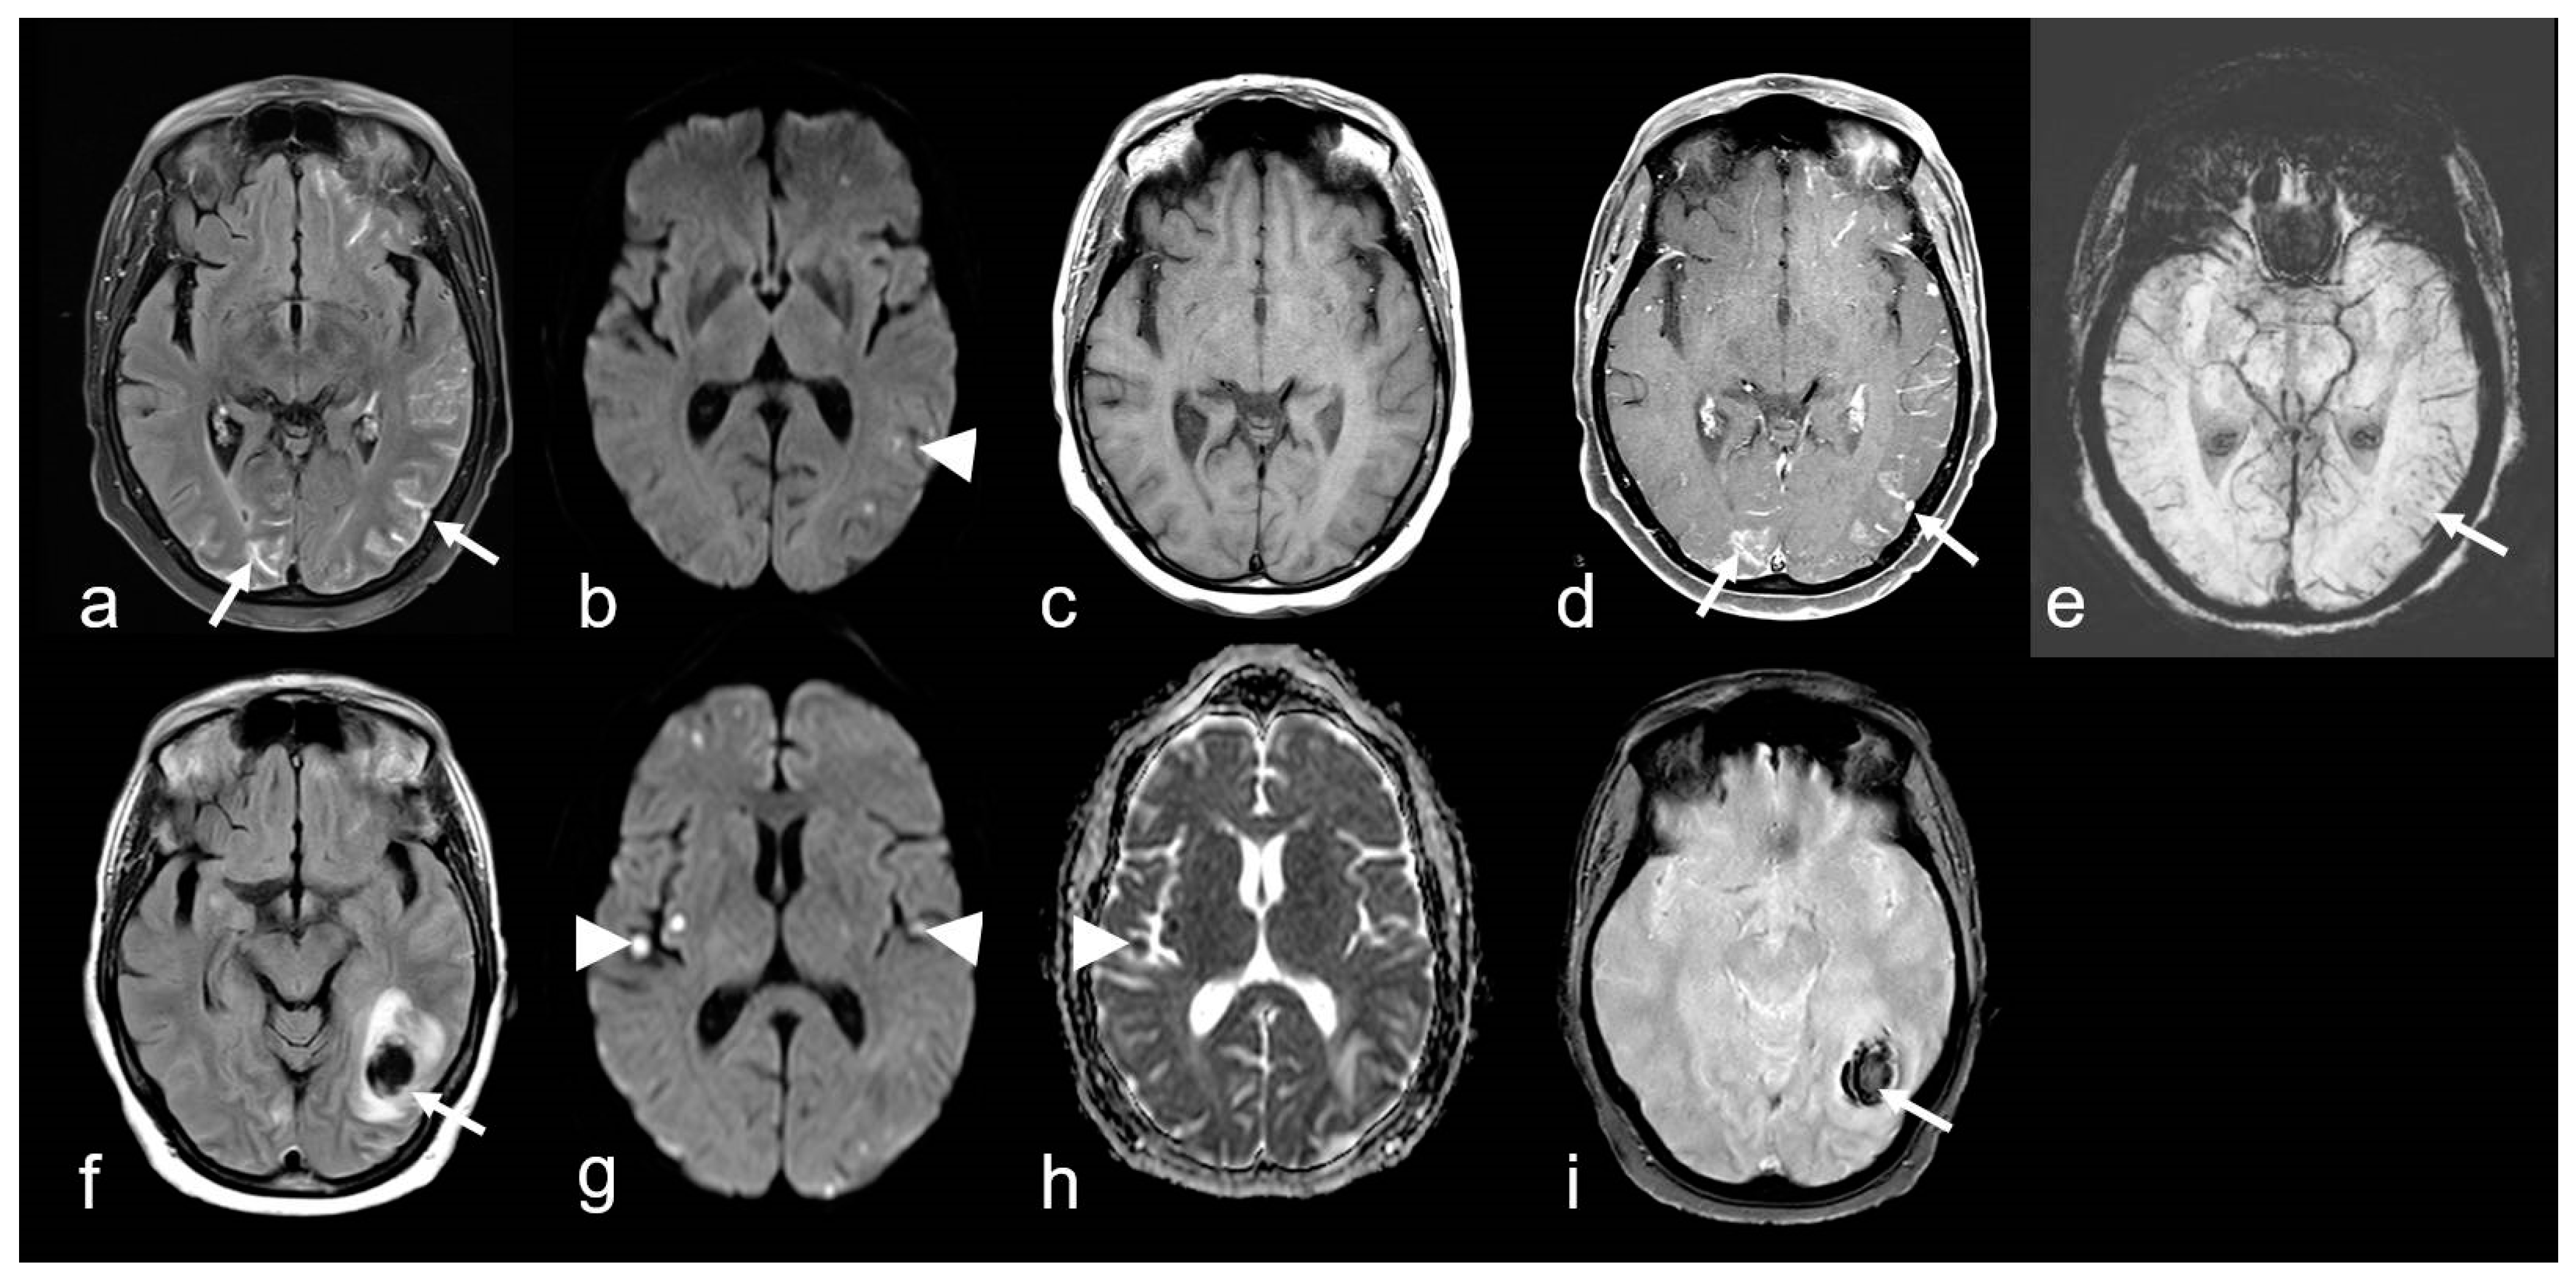

Figure 7.

A 68-year-old woman suffering from progressive dizziness and visual blurring for several weeks (upper row) and acute deterioration (lower row) due to cerebral amyloid angiopathy-related inflammation (CAA-ri) with associated vasculitis (amyloid-beta-related angiitis, ABRA). (a–e): Multifocal hyperintense sulcal effusions ((a), arrow; fluid-attenuated inversion recovery (FLAIR)), focal small lesions with restricted diffusion temporo-parietal left ((b), arrowhead; diffusion-weighted imaging (DWI, b = 1000 s/mm2)), distinct multifocal leptomeningeal enhancement ((d), arrow; (c,d): T1 WI before (c) and after (d) contrast agent application); (e): multiple microbleeds (arrow, susceptibility-weighted imaging (SWI)). (f–i): Subacute lobar intracerebral hemorrhage (ICH; (f), arrow); (g,h): new cortical / subcortical infarcts ((g,h): arrowhead; DWI, b = 1000 s/mm2, apparent diffusion coefficient (ADC) map); (g): T2* WI demonstrating inhomogeneous signal loss (arrow); MRI 1.5 T Intera, Philips Healthcare.